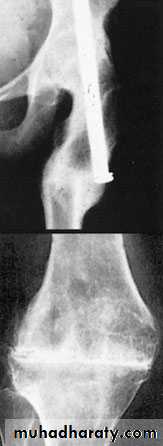

3- realignment osteotomy

3- realignment osteotomy like proximal tibial osteotomy: Osteoarthritis usually affects the inside half (medial compartment) of the knee . This can lead to the lower extremity becoming slightly bowlegged or a genu varum deformity.Osteotomy decrease venous congestion, removed fibrosed sensory end , increased blood supply ,due to fracture induction, and re-aligning the angles (this places more of the weight-bearing force into a healthier compartment ).

A wedge of bone is removed or added to the upper tibia. A staple or plate and screws are used to hold the bone in place until it heals